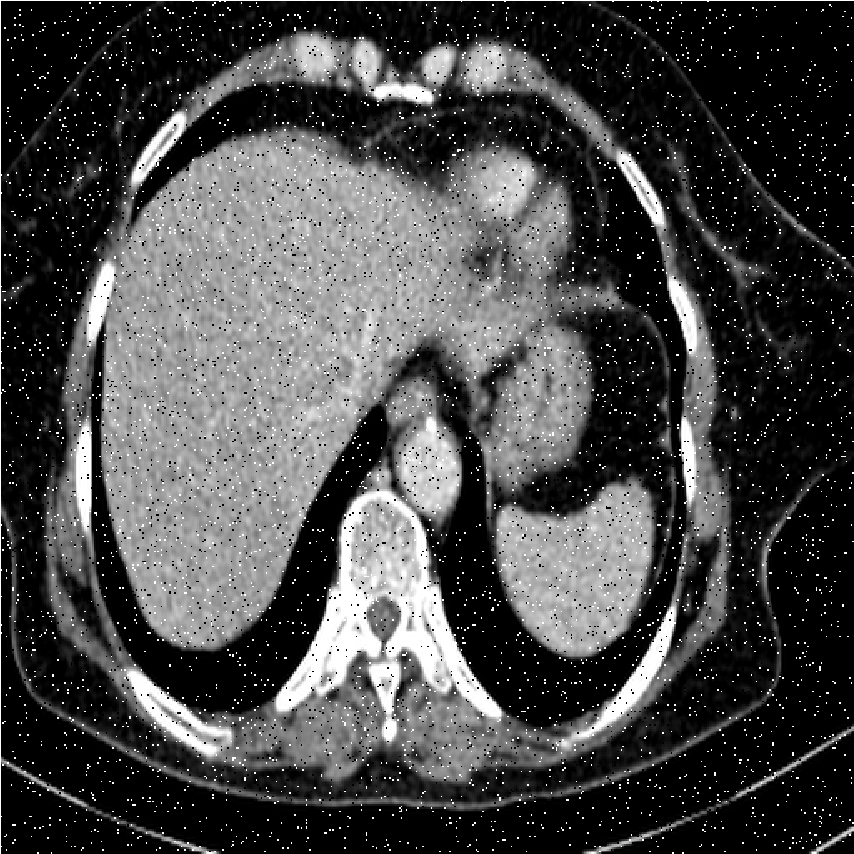

We performed extensive numerical simulations to examine the performance of the aforementioned denoising methods. For this purpose, we used a pixel grayscale CT scan image, shown in Fig. 2a. Noisy versions of this image were created by adding different types of noise at various strengths. The noise types considered are Gaussian noise, uniform noise, salt and pepper noise, and Poisson noise. The following subsections present and explore the results obtained from the various denoising methods. All computational programming were carried out using Mathematica 12.0.

[b)Gaussian]

[c)Uniform]

[d)Poisson]

[e)Salt Pepper]

This finding highlights a critical principle in image processing: the implementation strategy (global vs. local processing) can be as important as the choice of transform itself. Future work could explore local or adaptive wavelet thresholding schemes (e.g., context modeling, spatially varying thresholds) to leverage the strengths of wavelets while incorporating the local adaptability that made DFCT successful in this study. Figs. 8-11 show visual comparison of denoising results for the four kinds of noise. In the Figs. 8-11 the left image is noisy input image, the middle image is denoised image using the best wavelet method (BIOS wavelet with Hyperbola threshold for case of Gaussian and uniform noise, BIOS wavelet for Poisson noise and Daubechies wavelet with SURELevel for salt-and-pepper noise) and, the right image is denoised using DFCT.